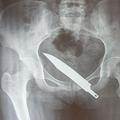

Bolečina po ropu Tatovi v zadnjici pustili nož Zaradi neznosnih bolečin je Kitajka po več mesecih ugotovila, da so ji roparji v zadnjici pustili neprijeten spominek.